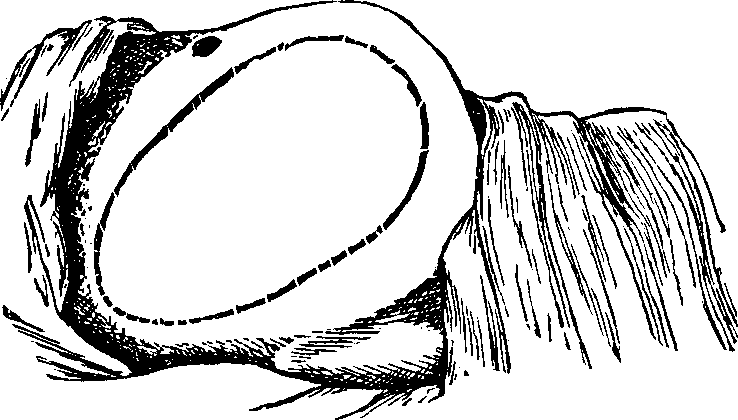

Fig.

17. Anatomy of a joint, 1, 1. Bones of a joint. 2, 2. Cartilage. 3, 3, 3, 3. Synovial

membrane.